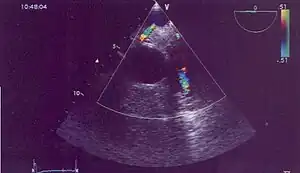

| Possible communication between left coronary artery and pulmonary artery in a 45-year-old woman with Bland-White-Garland syndrome. | |

Historically ALCAPA was diagnosed with conventional angiography. Today echocardiography is easily used. It can provide direct visualisation of the anomalous coronary artery and other associated structural abnormalities, and it can also assess myocardial function .The use of pulse and color-flow doppler can sometimes visualise reversal flow in the pulmonic artery. Other non-invasive methods used are computed tomography (CT) as well as magnetic resonance imaging (MRI) which enable a direct visualisation of the arteries as well as the myocardial viability.[3]